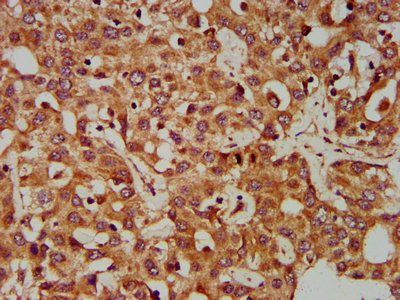

IHC image of CSB-PA857024LA01HU diluted at 1:400 and staining in paraffin-embedded human liver cancer performed on a Leica BondTM system. After dewaxing and hydration, antigen retrieval was mediated by high pressure in a citrate buffer (pH 6.0). Section was blocked with 10% normal goat serum 30min at RT. Then primary antibody (1% BSA) was incubated at 4°C overnight. The primary is detected by a biotinylated secondary antibody and visualized using an HRP conjugated SP system.